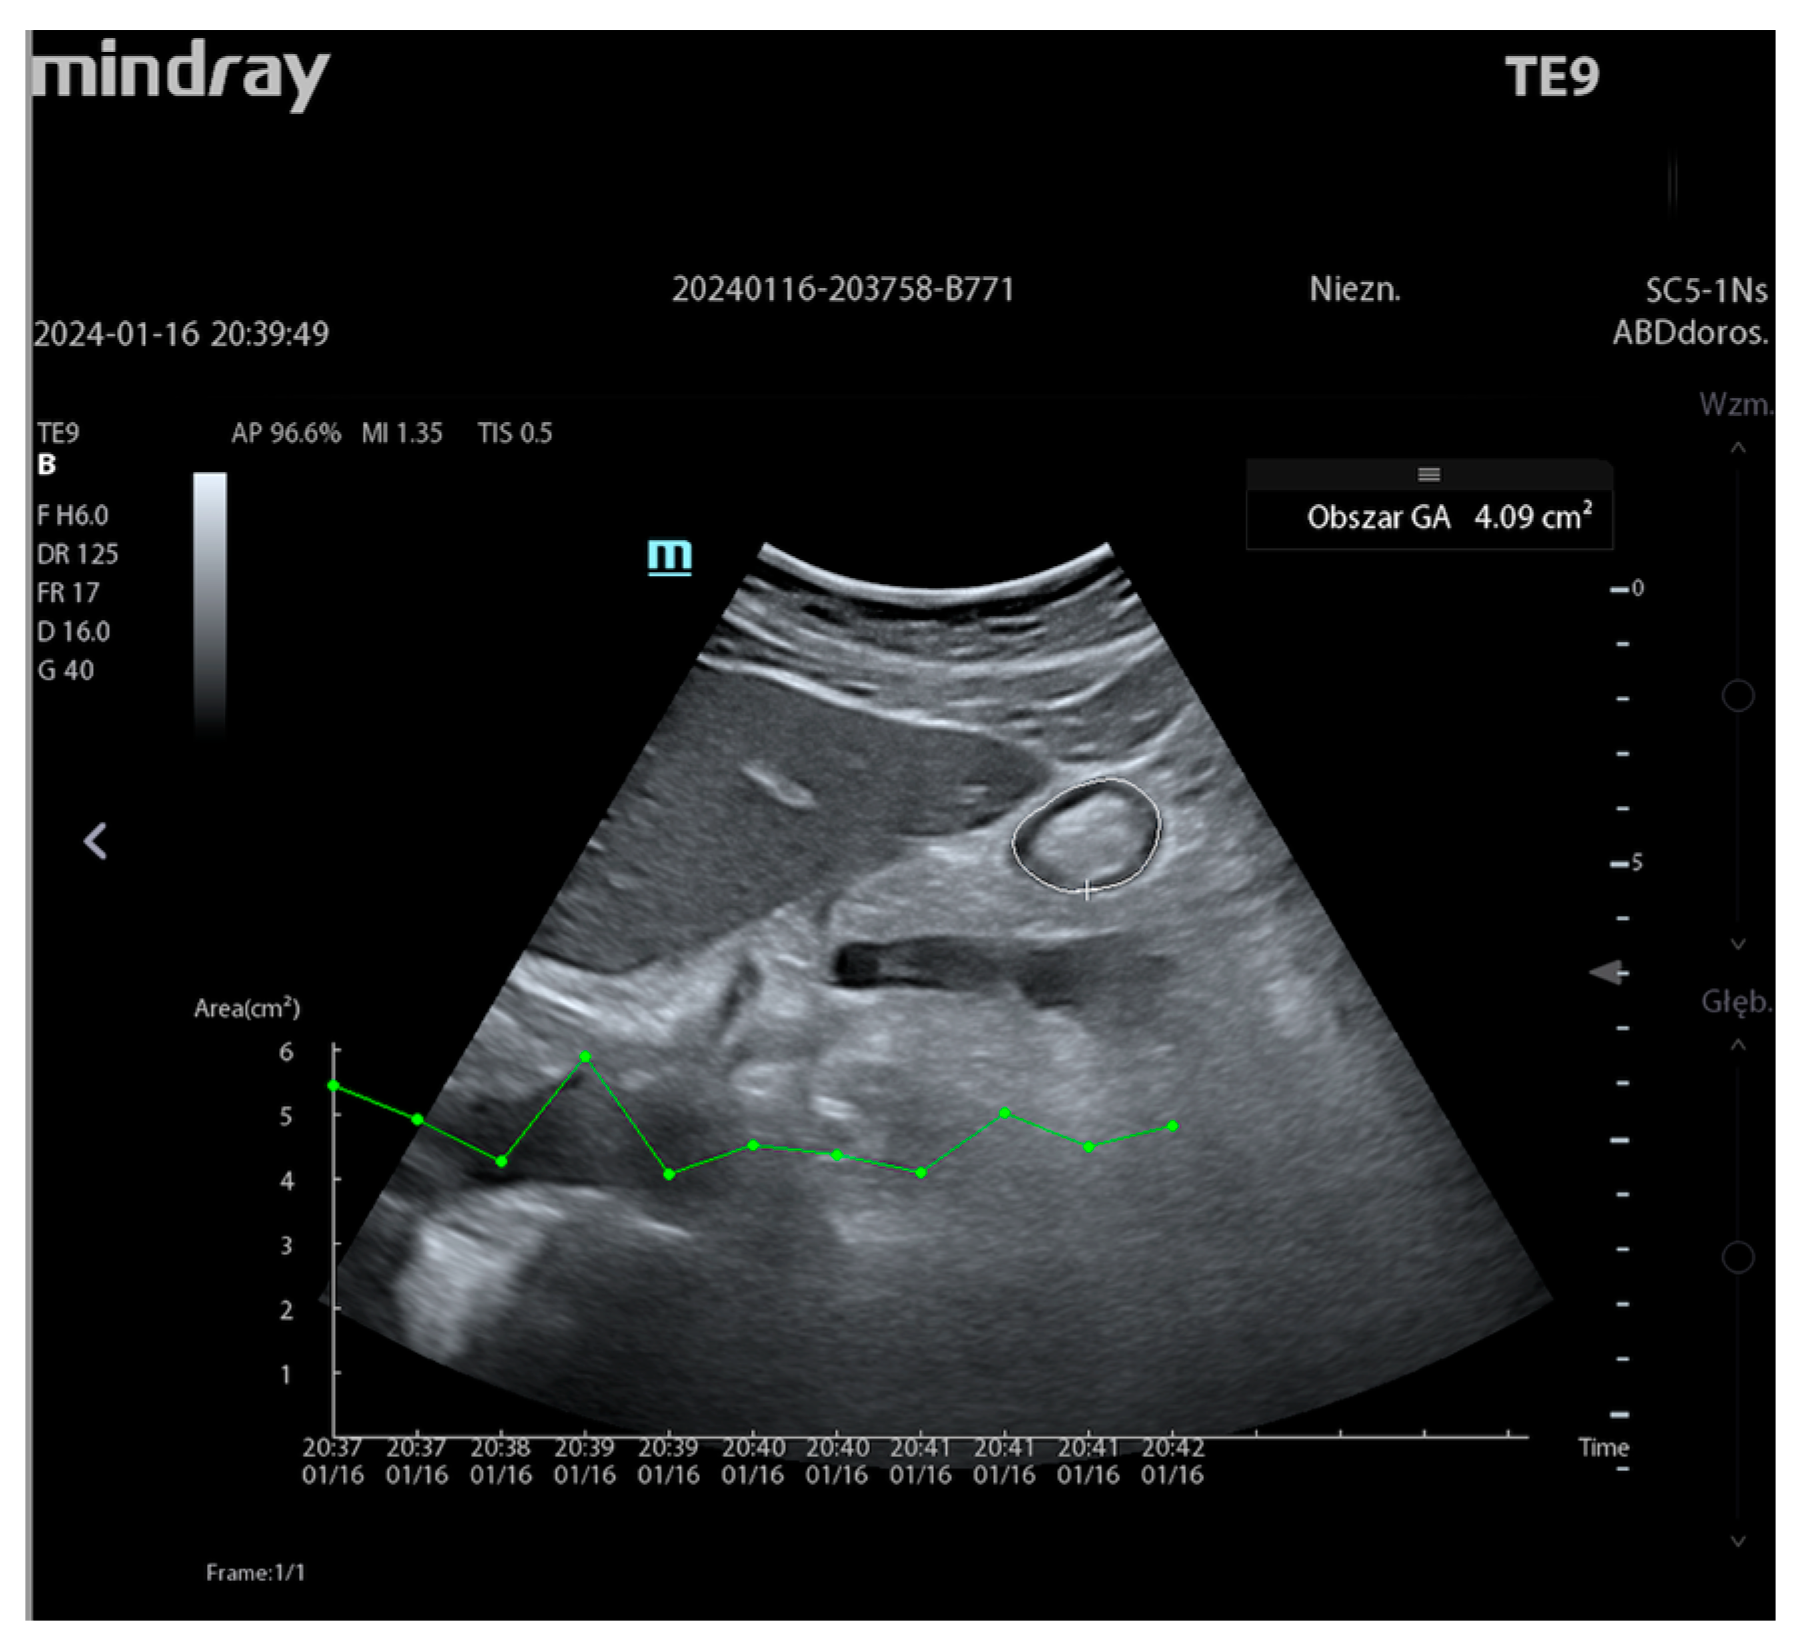

| Auto Gastric Antrum | Mindray | automatic measurement of gastric contents | Gastric examination |